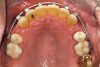

Figure 4b  Progress photo and panorex 9 months after corticotomies were performed on Nos. 6 through 11 (B and C). Previous extraction sites were reopened orthodontically to improve function and fill lip support. Incisal edges were restored provisionally with composite resin. Note that despite the creation of adequate spaces to replace missing teeth, there is inadequate room for placement of dental implants because of severe tipping of all the anterior teeth. Osteotomy SFOT may have been a better choice because it would have allowed needed alveoloskeletal correction (without excessive tipping) instead of the primarily dentoalveolar correction common in corticotomy SFOT. Restorative dentist: Brad Jones, DDS.

Figure 4b

Figure 4c  Progress photo and panorex 9 months after corticotomies were performed on Nos. 6 through 11 (B and C). Previous extraction sites were reopened orthodontically to improve function and fill lip support. Incisal edges were restored provisionally with composite resin. Note that despite the creation of adequate spaces to replace missing teeth, there is inadequate room for placement of dental implants because of severe tipping of all the anterior teeth. Osteotomy SFOT may have been a better choice because it would have allowed needed alveoloskeletal correction (without excessive tipping) instead of the primarily dentoalveolar correction common in corticotomy SFOT. Restorative dentist: Brad Jones, DDS.

Figure 4c